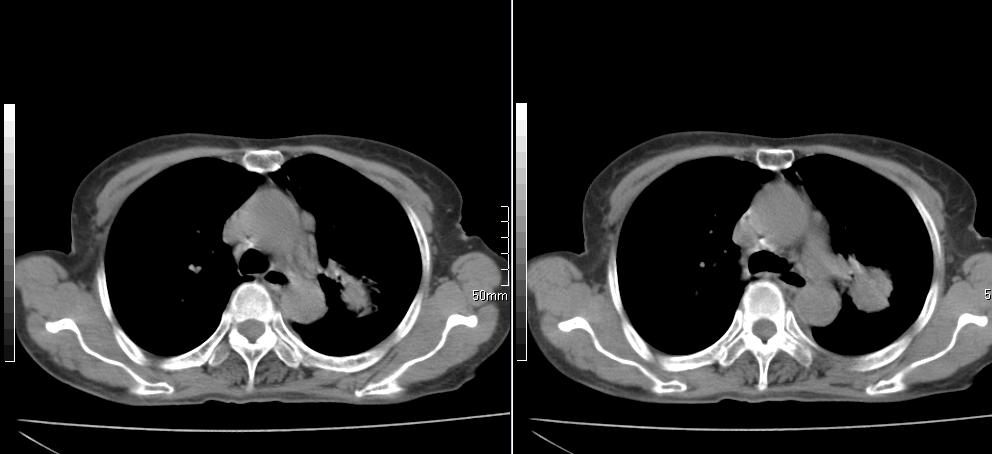

标题: CT26857:女,60岁,胃部不适前来就诊,不咳嗽,乏力,胸椎 [打印本页]

1、胸椎有骨质破坏伴周软组织,考虑胸椎转移。2、考虑左肺上叶尖后段支气管开口区周围型肺癌可能。

1、胸椎有骨质破坏伴周软组织,考虑胸椎转移。2、考虑左肺上叶尖后段支气管开口区周围型肺癌可能。建议行纤支镜检查!

1、胸椎有骨质破坏伴周软组织,考虑胸椎转移。2、考虑左肺中央型肺癌可能。

支持中央型肺癌,胸椎转移。

1)考虑左肺中央型肺癌。2)胸椎转移瘤不排除;建议行mri检查。